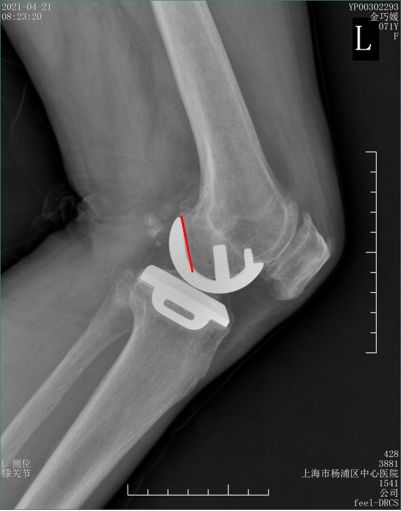

辨认bearing内的标识(X-ray侧位)

bearing 内的标识:点和线段“ .—. ”线段显示为“—”在前,点显示为“.”在后

辨认bearing内的标识(透视片侧位)

bearing 内的标识:点和线段“ .—. ” 线段显示为“—”在前;点显示为“.”在后